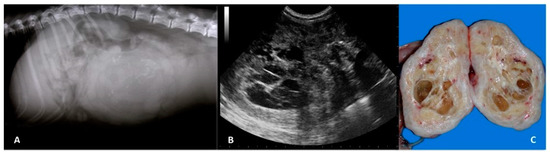

Imaging of Ovarian Neoplasia